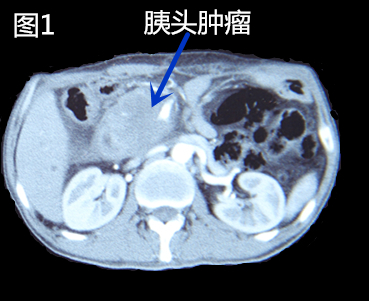

患者鲍先生,现年50岁,既往因“胰腺恶性肿瘤、重度黄疸”于肝胆胰腺外科行“开腹胰腺肿瘤射频消融、胃肠吻合、胆肠吻合术”。术后黄疸消褪,基本情况明显改善,半年后再次复查CT,提示胰头肿瘤较前增大(图1),这个消息使鲍某及其家人陷入了更深的绝望——上次手术可能已经是最后一次机会了,这次的复发比上次情况更加凶险。当李晓勇教授告知其可以考虑一种全新的纳米刀手术治疗胰腺癌时,鲍某的心中再度燃起生的希望。